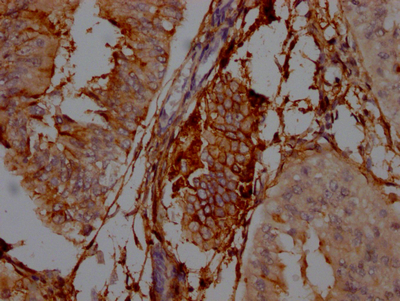

ELISA, WB, IHC

ELISA, WB, IHC, IF, FC

ELISA, IHC